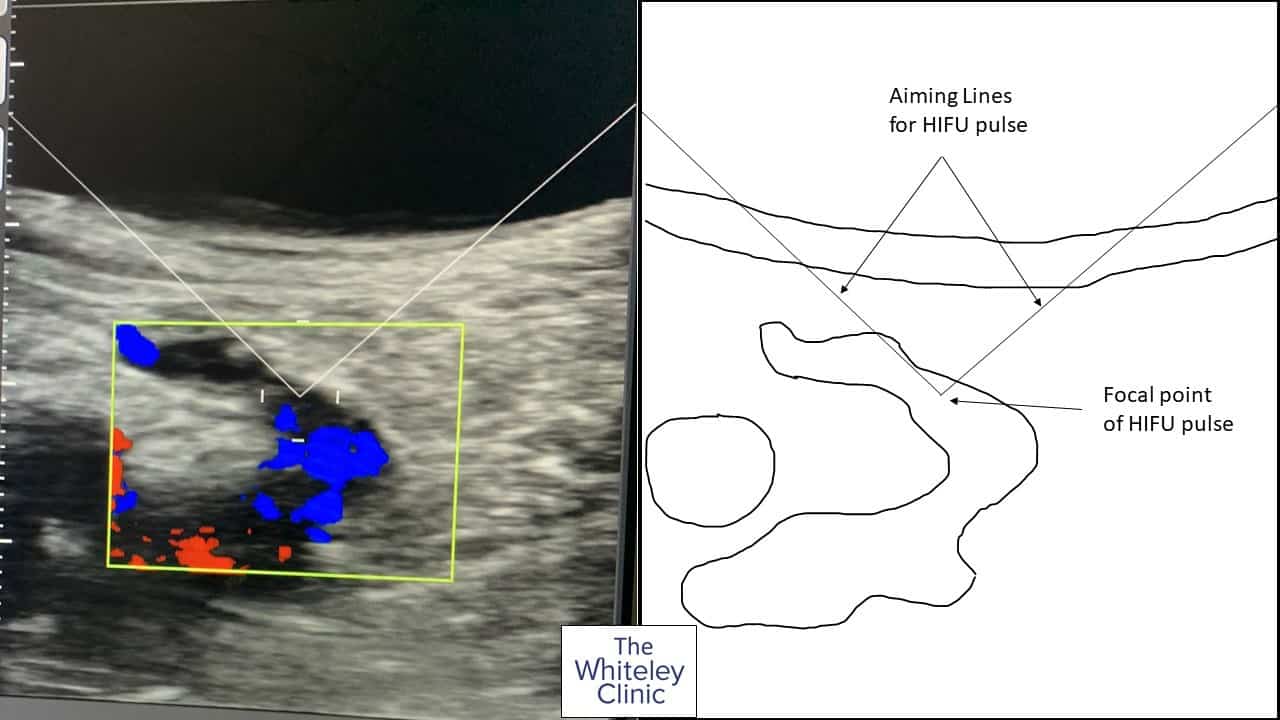

HIFU treatment of recurrent varicose veins - HIFU energy being aimed by ultrasound and on-screen guides

Although the hedgehog technique is minimally invasive, it still does need multiple cannulas put into the target veins under local anaesthetic. The laser or radiofrequency is then passed down each cannula in turn and the vein destroyed with heat. Today, we can do the same operation completely noninvasively. As is shown in these pictures, we can identify the regrown saphenofemoral junction on ultrasound. We can then place the HIFU aiming guides directly on the part of the vein we wish to ablate (close). Using just a little local anaesthetic for the tender scar tissue, several pulses can then be passed across the skin and focused onto the recurrent varicose veins. Working our way along the area of recurrent varicose veins, we can then completely seal the regrown junction. This stops all of the reflux of blood from the femoral vein into the recurrent varicose veins through the saphenofemoral junction. Now that the reflux is stopped, foam sclerotherapy can be used in the future if needed to get rid of any other recurrent varicose veins further down the leg. An additional advantage of the HIFU Echotherapy treatment is that the patient walked home directly after the treatment and did not even need to wear a stocking! For more information about HIFU Echotherapy, please contact us.